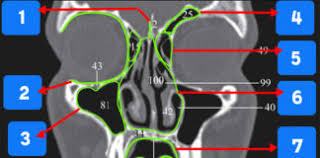

Ct Anatomy Quiz

Ct Anatomy Quiz from www.denteach.com